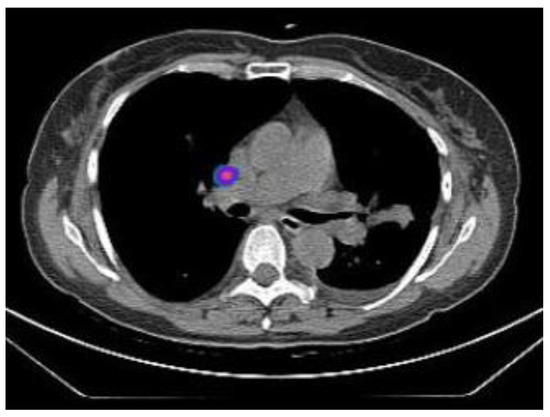

2.2.1. TIME 0: Lesion marking and SPECT Analysis